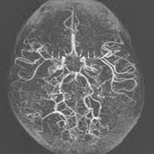

모야모야병(Moyamoya disease)

관련질환

뇌경색

,

자발성 두개강 내 출혈

일과성 뇌허혈증